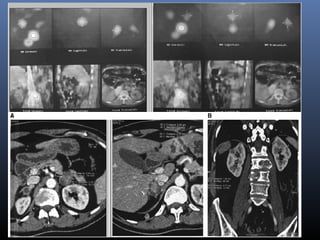

52 yr male a known case of follicular carcinoma of thyroid was

administered 182 mCi of radioiodine a month after total

thyroidectomy.

Post therapy scan: Radioiodine uptake in apex of left lung

CT guided biopsy of mass revealed mucinous BAC. Surgery was ruled out so he was

given chemotherapy without benefit. Since the lesion continued to show I-131 uptake a

high dose radioiodine therapy was given with 209 mCi I-131. Follow up CT scan

showed 1 cm all round reduction of the mass suggesting a possibility of this therapeutic

option in non thyroidal tumors that may concentrate radioiodine

30 yr male underwent total

thyroidectomy followed by RAI

therapy for PTC.

Presented 2 decades later with

LBA. MRI s/o multiple vertebral

mets. WB RAI scan showed

extensive mets and suspicious

abdominal foci.

CT guided biopsy from left adrenal focus confirmed

metastasis from carcinoma of thyroid.

Metastases to both renal and adrenal have been

rarely reported from carcinoma of thyroid and to the

best of our knowledge this the second such case.